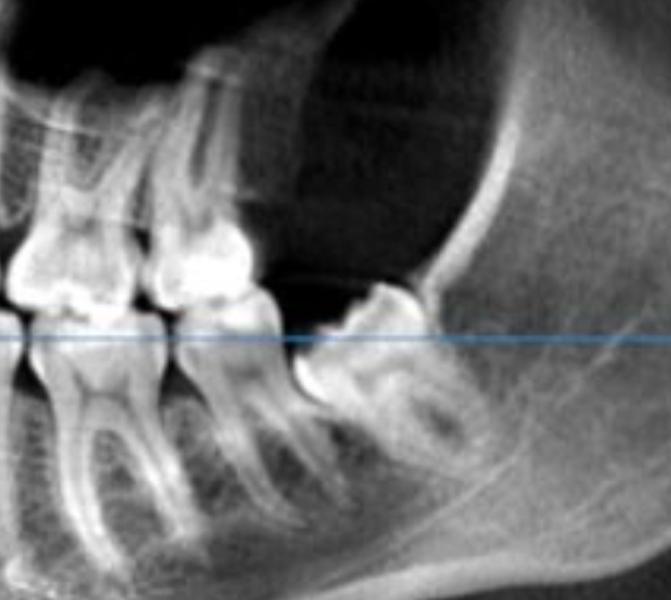

Подскажите, как удаляли нижних восьмерок? Пошла сделать КТ и мне сказали, что удалять надо все 3 оставшиеся восьмерки. Если к верхнему претензий нет, то нижние напрягают. Один прикрыт костью скраю и болит при жевании. Видимо пилить придется.. Засранец конкретно с фото вообще никак не беспокоит, но сказали, что надо убирать. Точно ли есть смысл?

Такой удалять, он давит на семерку. Удалить можно два одновременно, но только на одной стороне нижний и верхний)) у самой нижние так лежат. Верхние удаляла в гос поликлинике, где это на поток поставлено. 10 мин зуба нет, но это верхние, их легче. С нижними тоже пойду в факультетские, у них такое на дню по 10 раз дергают.

Тот, что на фото, будет лезть и сдвинет передние зубы, как у меня это случилось🥲 Ровные зубы были, а стали нет(

А тот который не болит, тоже под десной. Но вот думаю не испортит ли он соседа, или мне жути нагнали

@lisonkalisa вот кстати, про соседа. Я свой долго не удаляла и у меня он начал портить корни соседнего зуба. Теперь скорее всего надо будет этот зуб удалять и ставить имплант, потому что при нажатии или любом воздействии зуб болит сильно. Теперь надо решиться на эту процелуру😣